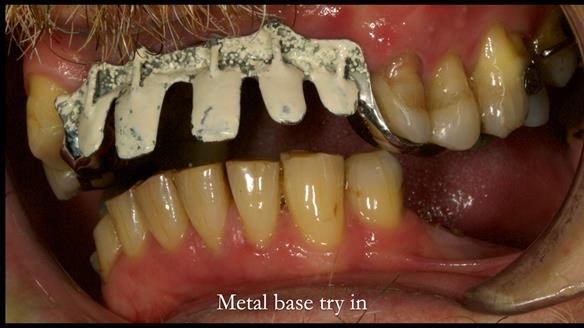

Keith’s case was one of the most challenging and rewarding cases I’ve treated this year. This 64 year old man presented with ill-fitting acrylic partial dentures that lacked stability, retention, and aesthetics. They constantly broke. He had lost the upper front teeth in a road traffic accident in his early 20s. The unopposed teeth had erupted, taking up space. After careful planning, we made a durable, metal-based upper partial denture/splint to address his dental concerns. He loved the outcome.

1. Denture design: A custom cobalt-chromium framework was Scandinavian-designed to maximise stability, protect the remaining teeth, and allow for future additions if needed.

Keith’s denture incorporated a Duracetal shell clasp on upper right first premolar (Myerson), which are designed to be virtually visible, providing a more aesthetic solution while enhancing patient comfort. The Scandinavian-inspired approach, based in modern removable prosthodontic techniques, ensured the denture was not only durable but also visually pleasing. Additionally, the design was carefully planned to allow for future modifications, ensuring that if Keith loses additional teeth, the denture can be adapted rather than replaced entirely.